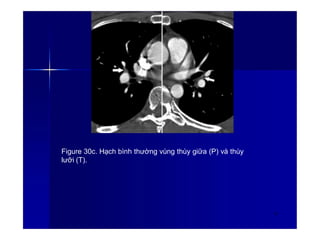

Figure 30a. Hạch bình thường vùng rốn phổi 2

Figure 30c. Hạch bình thường vùng thùy giữa (P) và thùy

lưỡi (T).

42